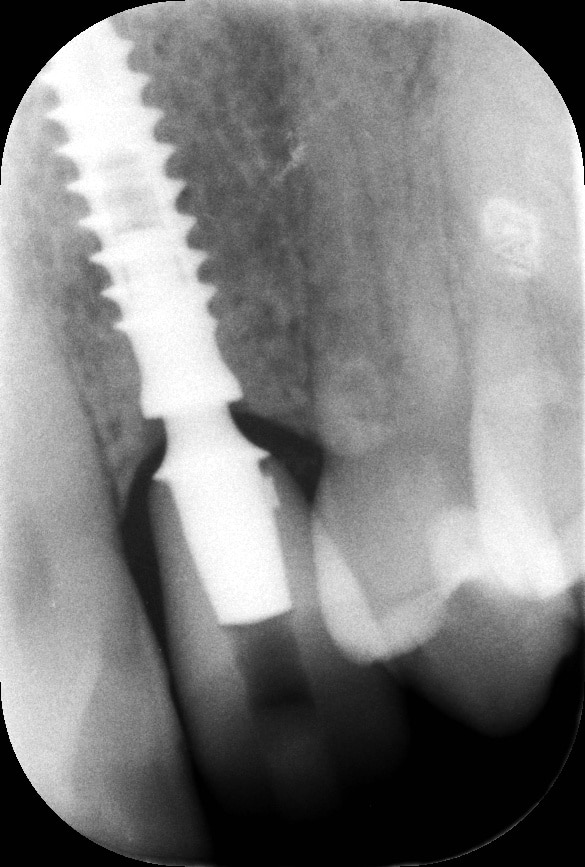

La pz N.G. di anni 52 (ASA 1) viene visitata nel mese di settembre 2017 per la mobilità ed inestetismo dell’elemento protesico 22, (foto iniziali sequenza 1) si evidenzia una frattura parziale della radice, si decide per l’estrazione ( foto sequenza 2) e sostituzione dell’elemento con un restauro implanto-protesico. Purtroppo la scarsa quota ossea apicale all’alveolo post-estrattivo (foto 2 rx) e l’alta valenza estetica dell’elemento ci rende cauti e si programma una socket preservation post estrattiva con l’ausilio delle membrane di prf (foto prf e socket sequenza 3 e 4). Durente i 5 mesi di guarigione la pz porta una protesi parziale mobile (foto 5,2) , a guarigione del sito post estrattivo si evidenzia una buona conservazione dei volumi osseo-gengivali,(foto guarigione sequenza 6) se pur presente una recessione distale all’elemnto 21.Nel mese di febbraio 2018 si procede all’inserimento di un impianto max-stability 3,75x12mm disegnando un lembo anticipato palatino per consentire un aumento dei tessuti vestibolari suturando con tecnica rool flap e trasformando l’elemento parziale mobile in una corona singola a carico immediato sul moncone temporameo applicando i concetti protesici bopt , (foto impianto moncone protesi provvisoria sequenza foto 7-8-9). Durante il periodo di maturazione dei tessuti molli vengono apportate opportune modifiche ai profili del provvisorio al fine di dare maggior spazio al tessuto gengivale, ( fotosequenza 10).Dopo circa 2 mesi dal protesizzazione provvisoria si è proceduto alla realizzazione del manufatto protesico con tecnica chair side sirona con l’ausilio del t-base (foto sequenza 11-12-13), realizzando in una sola seduta una corona in disilicato, ottenendo un risultato più che soddisfacente (Foto 14). Nel controllo a 3 mesi dal carico definitivo si apprezza la perfetta conservazione dei livelli ossei e gengivali. (foto sequenza 15).concludo con un follow up a 18 . Tengo a sottolineare che un caso come questo è stato conducibile con buoni risultati solo grazie alla piena fiducia della pz e alla sua massima motivazione e collaborazione. Ad oggi la pz sorride soddisfatta del risultato. E questo rappresenta la massima ricompensa di chi dedica tutto se stesso alla professione.

rx follow up 18 month post loading